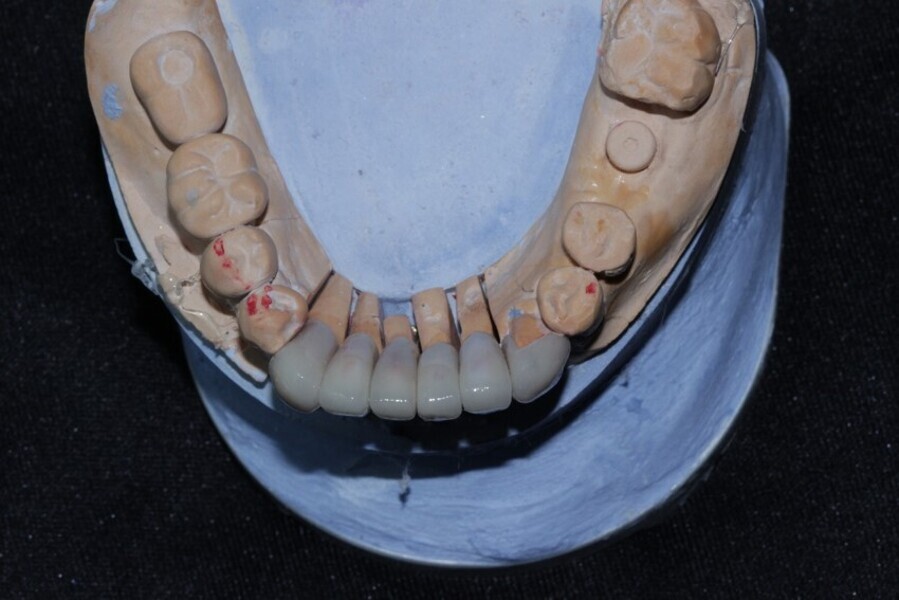

Figure 14 Diagnostic wax up as per digital smile designing planning

Figure 15 Diagnostic wax up as per digital smile designing planning